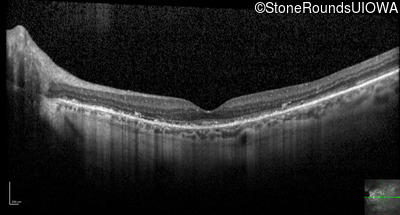

Optical Coherence Tomography - Right - 20/25 +1

Exemplar / OCT Stack

OCT Stack